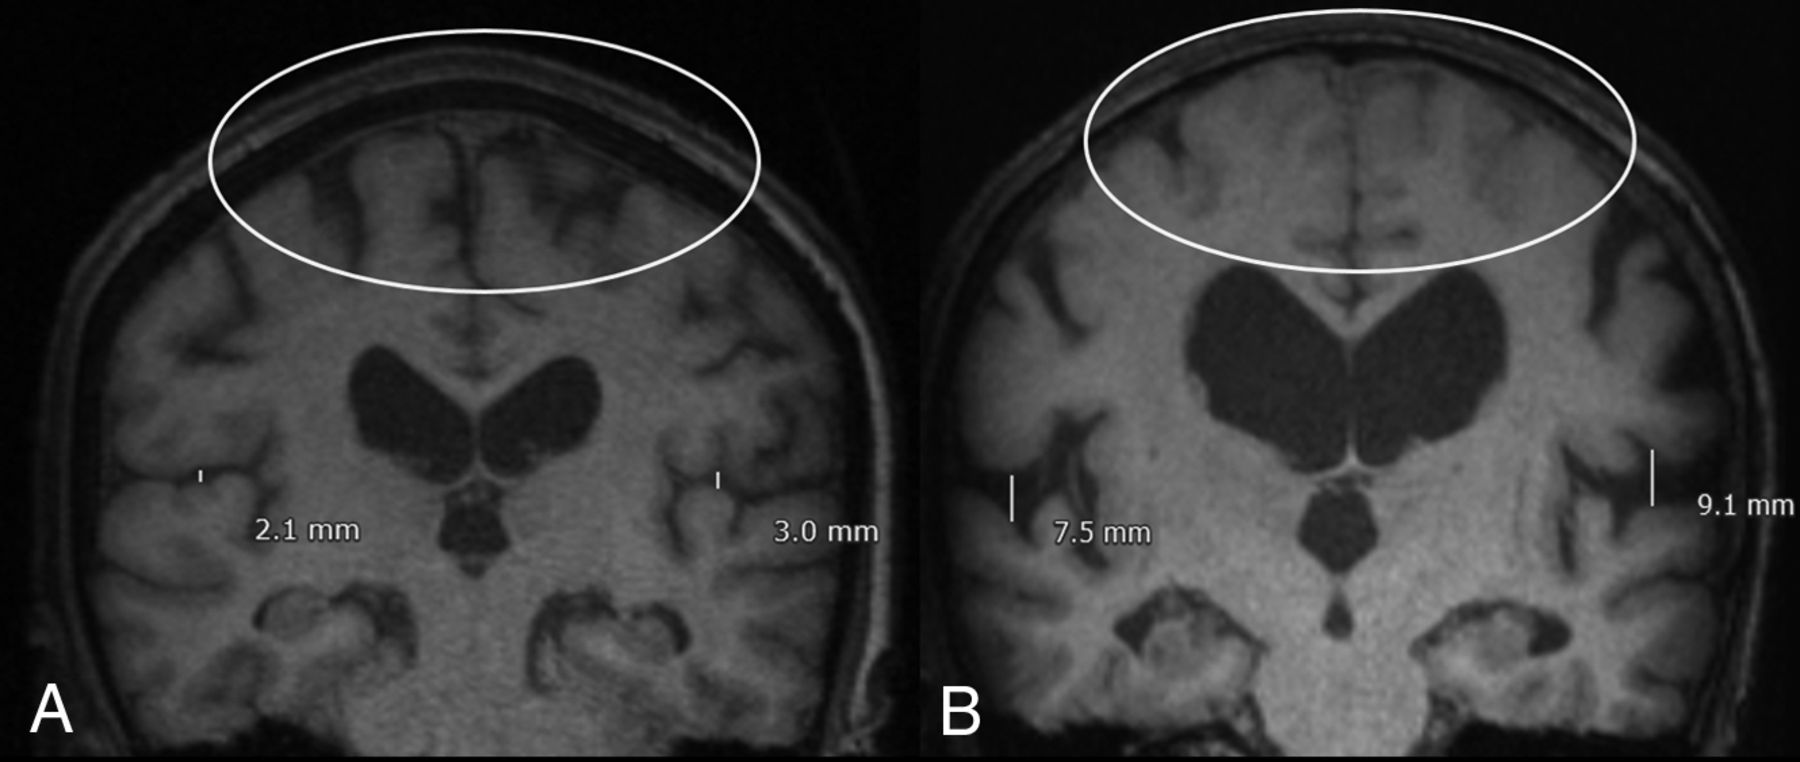

Patients surgically treated for adult hydrocephalus during an 11-year period (2003–2014) were included. Following blinded neuroradiology review of preoperative imaging for 162 adult patients surgically treated for hydrocephalus, 29 patients had partial features of DESH without fulfilling the complete DESH criteria and were excluded from this study. Of the remaining 133, ninety-six (72.2%) did not meet any DESH criteria and 37 (27.8%) had all DESH features present (Figure and Table 1). Of the 133 patients included in this study, 68.4% were men. The mean age at shunting was 71.7 years (range, 53–80 years) (Table 1).

Characteristic imaging and classification for patients with adult hydrocephalus. A, Absence of DESH. B, DESH present: Sylvian fissure enlargement and tight high-convexity effacement are present. Both patients were treated with ventricular shunting and had improvement in symptoms. A scaled measurement of the Sylvian fissure is provided to illustrate the extent of fissure enlargement in this representative case. However, consistent with the defining features of DESH in the literature,3⇓–5 quantitative measurement was not used as scoring criterion during blinded neuroradiologist review.